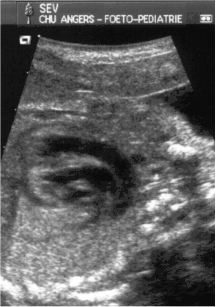

- le signe d'appel habituel est la perte du croisement des gros vaisseaux. Normalement, l'aorte et le tronc pulmonaire se croisent peu après leur sortie du cœur. Il est donc impossible de dérouler les deux vaisseaux sur un même plan de coupe. Quand l'aorte est vue longitudinalement, le tronc pulmonaire n'apparaît qu'en section transversale ("aorte en long, tronc pulmonaire en rond") et vice-versa. Dans la D-TGV simple, la plus fréquente, les vaisseaux ont un trajet parallèle et peuvent donc être visualisés longitudinalement simultanément.

- la confirmation est obtenue par l'analyse des gros vaisseaux et de leurs connexions aux ventricules. L'aorte est caractérisée par le fait qu'elle décrit une crosse, donne naissance aux vaisseaux à destinée céphalique et est le vaisseau qui monte le plus haut dans le thorax. Le tronc pulmonaire est caractérisé par sa bifurcation précoce en deux branches, les artères pulmonaires droite et gauche. Sur un cœur par ailleurs normal, le ventricule droit est situé en avant et à droite du ventricule gauche, le tronc pulmonaire est donc le vaisseau le plus antérieur. La TGV se caractérise par la position antérieure du vaisseau qui décrit la crosse et donne les vaisseaux céphaliques : l'aorte.